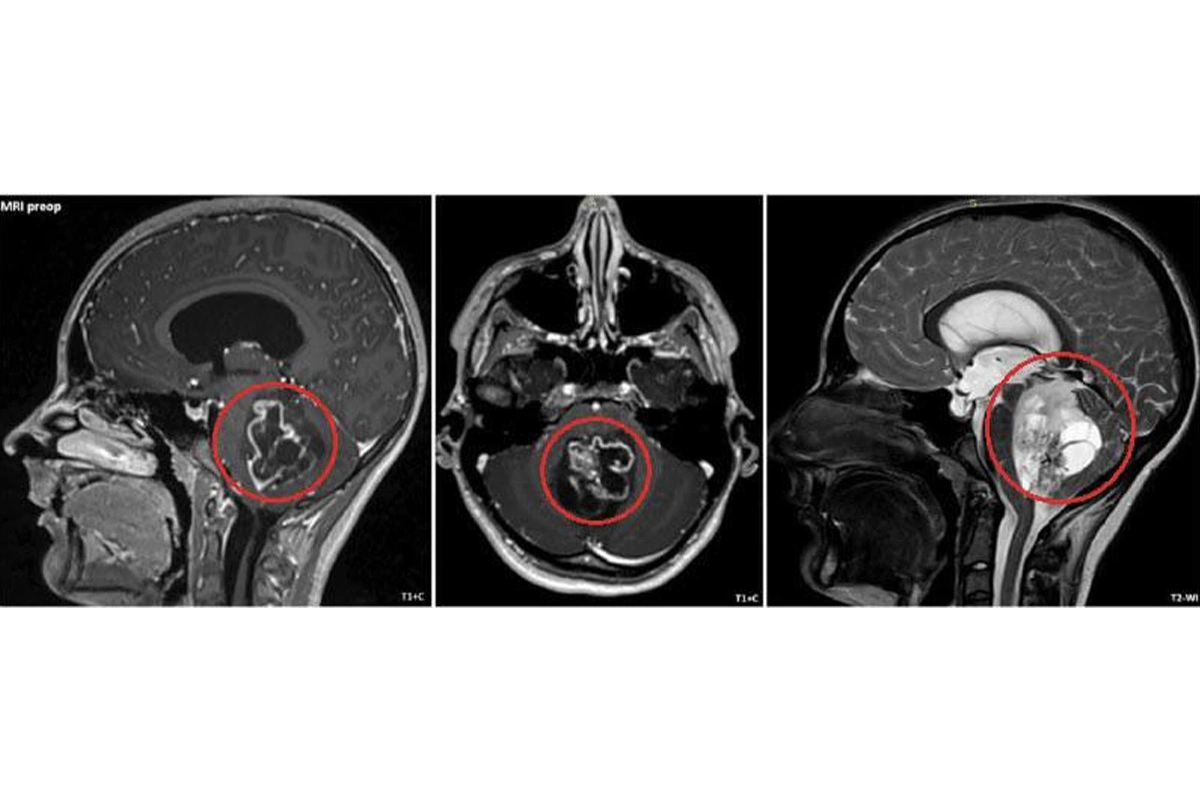

Пациент жаловался на постоянную тошноту и рвоту. Опухоль мозга обнаружили при углубленном обследовании, она находилась в задней черепной ямке. При такой локализации последующий рост опухоли мог обернуться нарушением жизненно важных функций.

Объемное новообразование — пятисантиметровая опухоль в задней черепной ямке